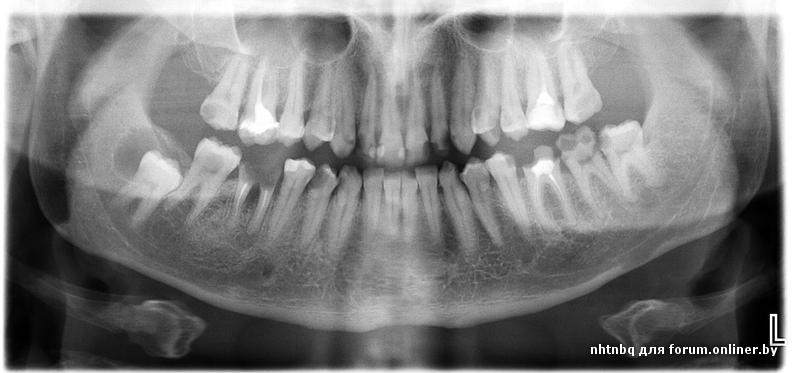

Здравствуйте, уважаемые врачи. Подскажите пожалуйста какие работы предстоит сделать.

Кратенько обозначим проблемы. Еще 26 реэндо

Thecbuh:Кратенько обозначим проблемы. Еще 26 реэндо

Эмм...Я вроде спросил что делать, а не какие у меня проблемы.

Лечить, удалять, протезировать.

Много лечить, удалять и тд . Вместо удаленных что захотите? Мосты или импланты? На передние пломбы с коронками или виниры(композитные/керамические)?

План лечения зависит еще и от ваших запросов

Примерно, такие-то удалять, протезировать, такие-то лечить, ставить коронки, такие-то лечить.

Понятно что, для детального плана нужен личный осмотр, знание запросов и возможностей, но примерные действия по каждому зубу вы же можете сказать.

Запросы простые: импланты, вставки коронки и "шоб смотрелось" (т.е. эстетика).

Во вторых. Предварительный план в данной ситуации можно составить только после очного осмотр. Окончательный же план протезирования будет после терапевтической подготовки.

В третьих по данному снимку можно составить 20 планов, а то и более планов лечения в зависимости от материальной обеспеченности.

nhtnbq, предварительно как-то так

Л-лечить

К- коронка

У- удалять